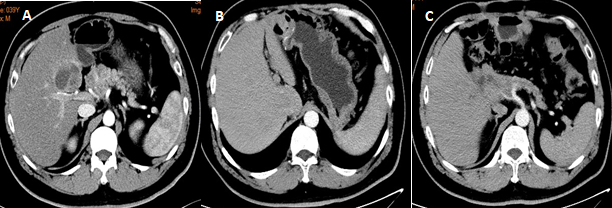

联合脏器或血管切除的扩大根治术

虽然胰腺神经内分泌肿瘤侵袭性弱于胰腺癌,但由于该类肿瘤常无临床症状,发现时往往肿瘤体积较大,所以肿瘤侵犯周围脏器或者重要血管的情况并不少见。联合血管切除在胰腺癌治疗中已经被广泛认可,同样在胰腺神经内分泌肿瘤上也适用(图5)。

图5 患者诊断为胰头部NET侵犯肠系膜上静脉,CAPTEM方案新辅助化疗后行根治性胰十二指肠切除+肠系膜上静脉重建+扩大腹腔淋巴结清扫。